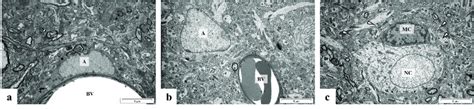

- The Synaptic Structure In The Ca1 Region Of Rat Hippocampus At ...

- | Ca1 Region Of The Mouse Hippocampus. (a) Area Of The Ca1 Region ...

- Histological Examination Of The Ca1 Region Of Rat Hippocampus Following ...